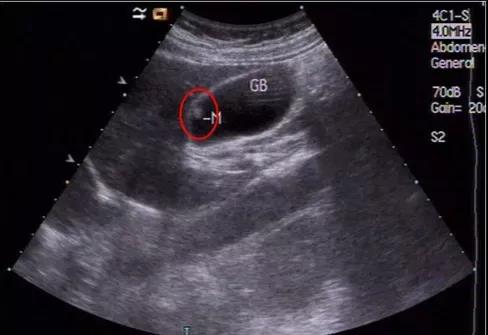

①看真假:真正可能變癌的是真息肉,假息肉不用管;

②看大?。?/strong>長到1厘米了就需要考慮手術,風險大了;